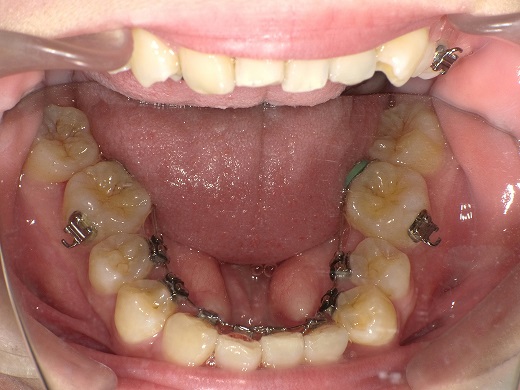

治療前上顎

治療中上顎

治療後上顎

治療後下顎